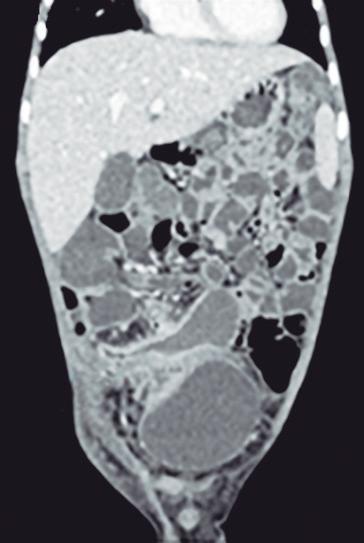

CASOS CLÍNICOS Biopsia guiada por ecoendoscopía como herramienta diagnóstica mínimamente invasiva para metástasis mesorrectal de carcinoma de células claras renales: reporte de caso

Nicole Marie Kahn, Mayra Florencia Defanti, Yanina Gabriela Carlino